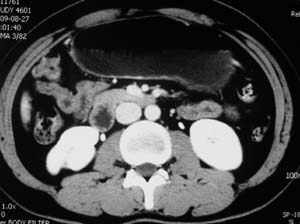

以下是引用子期在2010-3-19 20:47:00的发言:[br]血管畸形的ct增强应该有明显强化,本例并不相符合。本例双肾局部的略低密度影,累及肾盂,局部皮质明显变薄、内陷,增强扫描有轻度的强化,应考虑为炎性病变,患者为年轻男性,累及双肾的感染以结核较常见,可以没有明显的临床症状,尿中有时候也并不能查出什么;肾脓肿常有明显感染中毒症状,本例不符,另外一般的肾盂肾炎或肾小球肾炎通过小便就可确诊,其它还不能排除的是黄色肉芽肿性肾盂肾炎,然而单凭ct一般也很难鉴别。